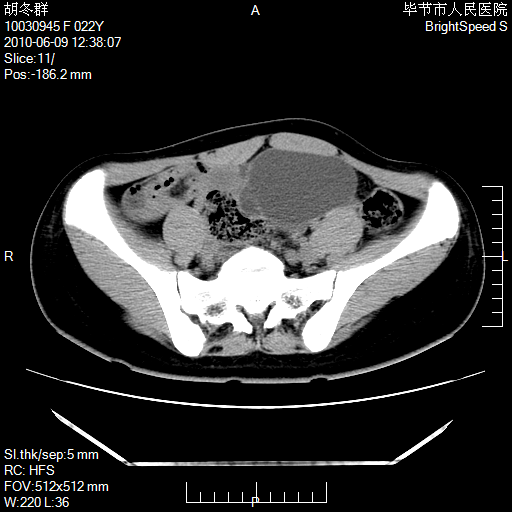

患者23岁,发现腹部包块3月。

盆腔内囊性占位;穿刺或者直接手术拿掉即可,不必紧张。

左侧卵巢囊腺瘤或囊腺癌

盆腔内囊性占位性病变;考虑左侧卵巢囊腺瘤。

有分隔、壁薄,支持考虑左侧卵巢囊腺瘤。

左侧卵巢浆液性囊腺瘤。

支持左侧附件区囊性占位,多考虑为囊腺瘤。

支持考虑左侧卵巢囊腺瘤;宫腔积液。

有分隔、壁薄,支持考虑左侧卵巢囊腺瘤。排尿后,膀胱缩小,由于重力作用,肿块下移就到了膀胱位置,很好理解。